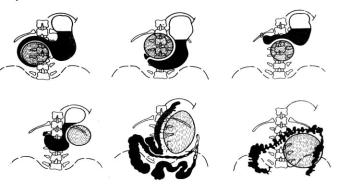

Весьма важные данные для определения размеров и локализации кист в поджелудочной железе можно получить при

рентгеноконтрастном исследовании органов желудочно-

кишечного тракта (рис.58). Особенно наглядную картину при кисте поджелудочной железы дает рентгенограмма контрастированного желудка, выполненная в боковой проекции

(О.О.Ден). На ней выявляется увеличение расстояния между передней поверхностью позвоночника и задней стенкой желудка.

Рис. 58. Схема взаимоотношения кист поджелудочной железы с органами желудочно-кишечного тракта при рентгенологическом исследовании